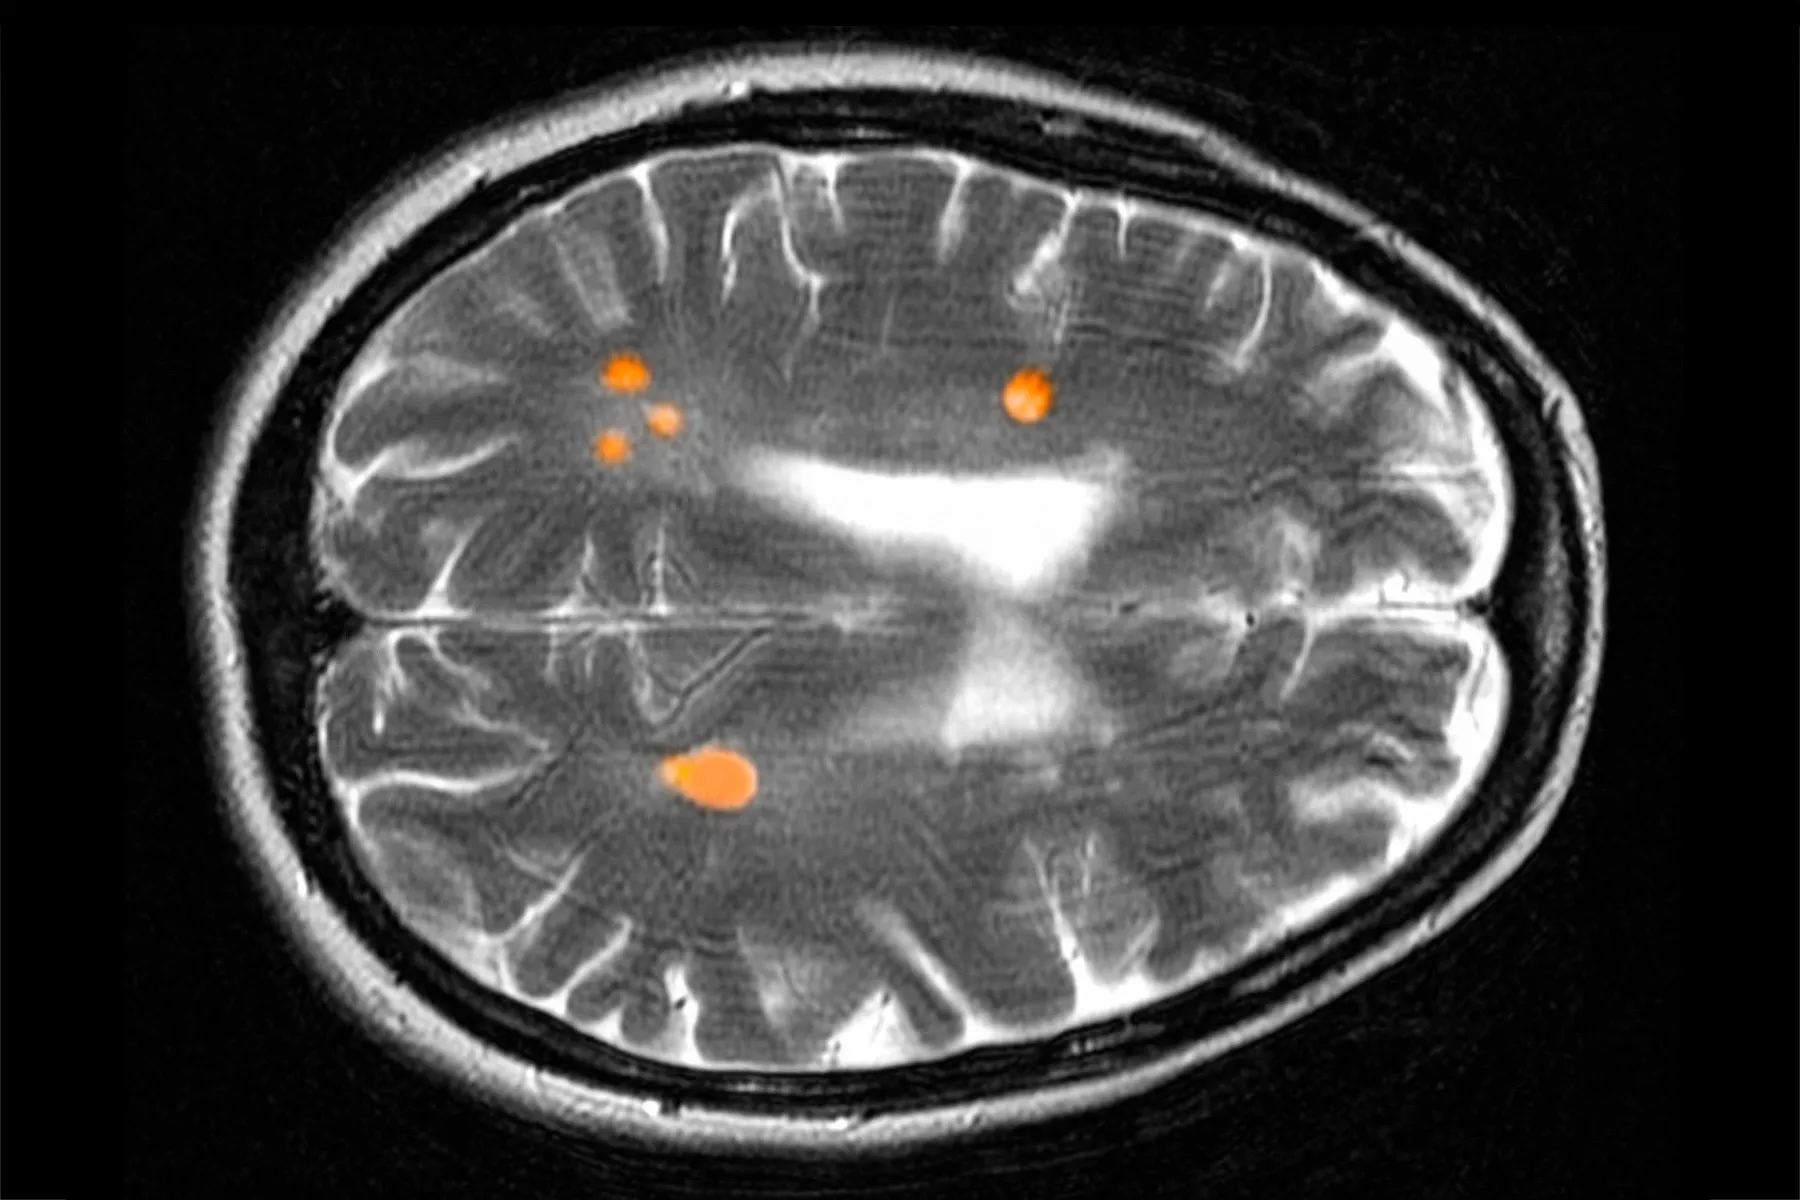

Ce-ar fi dacă un test de sânge ar putea semnala scleroza multiplă cu ani înainte de apariția simptomelor? În contextul recentelor progrese în diagnosticare și tratament – cum ar fi tehnicile avansate de RMN și terapiile puternice de depleție a celulelor B – cercetătorii afirmă că următoarea frontieră în îngrijirea sclerozei multiple ar putea fi prevenția. Aceștia cred că sunt pe drumul cel bun pentru a putea identifica boala înainte ca simptomele complete să apară, în ceea ce este cunoscut ca faza „prodromală”. Aceasta ar putea oferi medicilor ocazia de a interveni în anii adolescenței sau la începutul adulteții, prevenind astfel o afecțiune care poate duce la dizabilități grave sau declin neurologic.

Cu toate că vizitele suplimentare la medic pentru oboseală sau durere nu sunt motive pentru a solicita un RMN care să verifice leziunile cerebrale asociate sclerozei multiple, cercetătorii subliniază că este esențial să se dezvolte un test de sânge. O echipă de la Yale School of Medicine studiază persoanele cu un istoric familial puternic de scleroză multiplă, având ca scop dezvoltarea unui test de sânge. David Hafler, MD, profesor la Yale, a declarat că cheia este monitorizarea celor care nu au avut încă virusul Epstein-Barr (EBV) – o infecție care, de obicei, nu are simptome și se răspândește prin salivă și fluide corporale; infectează aproximativ 90% dintre oameni până la vârsta de 25 de ani. Un studiu de referință din 2022 a legat virusul de scleroză multiplă.

Chiar dacă un test de sânge ar putea fi dezvoltat, ar putea ridica provocări etice. Unele persoane au scleroză multiplă care nu este severă, sau au leziuni cerebrale identificate printr-un RMN solicitat din alte motive și nu dezvoltă niciodată simptome. În aceste scenarii, tratamentul de depleție a celulelor B ar putea să nu merite efectele secundare potențiale, cum ar fi un sistem imunitar slăbit. De asemenea, testarea genetică pentru scleroză multiplă este în curs de dezvoltare, devenind mai precisă.